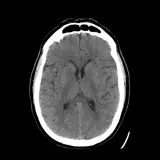

PACS์—์„œ ๊ธฐ๋Œ€ํ•  ์ˆ˜ ์žˆ๋Š” ๋ชจ๋“  ๋„๊ตฌ๋ฅผ ๊ฐ–์ถ˜ ์™„์ „ํ•œ ์ธํ„ฐ๋ž™ํ‹ฐ๋ธŒ ์ฆ๋ก€ — ์Šคํฌ๋กค, ์œˆ๋„์šฐ ์กฐ์ ˆ, ํ™•๋Œ€/์ถ•์†Œ, ํŒจ๋‹, ๊ณ„์ธก, ROI, ์ „์ฒด ํ™”๋ฉด ๋ชจ๋“œ๊นŒ์ง€ ์ง€์›ํ•ฉ๋‹ˆ๋‹ค.

์‹ค์ œ PACS ์›Œํฌ์Šคํ…Œ์ด์…˜์ฒ˜๋Ÿผ ์Šคํฌ๋กค, ํŒจ๋‹, ์œˆ๋„์šฐ ์กฐ์ ˆ, ํ™•๋Œ€/์ถ•์†Œ๊ฐ€ ๊ฐ€๋Šฅํ•ฉ๋‹ˆ๋‹ค